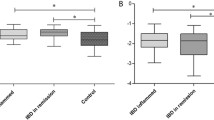

Left and right ventricular function and dimensions

There was no significant difference in LV or RV sizes, stroke volumes or ejection fractions between active and remission IBD-patients and HV. Patients in remission had a significantly higher myocardial mass index compared to HV. See Table 3 and Fig. 2 for CMR results.

Comparison of Cardiac MR derived markers of reverse myocardial remodelling in patients with inflammatory bowel disease in Active (”A”) and Remission (“R”) stages of disease with healthy control group (“C”). Left (A) and right (B) ventricular ejection fraction; C) Cardiac MR derived myocardial marker of diffuse fibrosis and inflammation (Global T1), * post-hoc testing, active vs. control: p < .01, D) Left ventricular myocardial mass, ** remission vs. control: p = .02, E) Global circumferential strain (%) and F) Global radial strain (%) as marker of left ventricular dysfunction, † post-hoc testing, active vs. control: p < .01; †† active vs. control: p < .01; Boxplots indicate median plus interquartile range (IQR) and whiskers connect the upper or lower quartile to the nonoutlier maximum or minimum value, outliers are defined as > 1.5 * IQR

Left ventricular systolic function: strain analysis

Patients with active disease but not in remission had significantly impaired GRS and GCS values compared to HV (GRS: Active: 23.40% ± 5.34%, Remission: 24.64% ± 5.78%, HV: 28.06% ± 4.92%; p < 0.01; GCS:—15.31% ± 2.38% vs.—15.93% ± 2.65% vs.—17.48% ± 2.02%, p < 0.01). Neither age, sex, type of medical treatment, IBD subtype, activity index nor time since initial diagnosis was associated with GLS, GRS or GCS (all p > 0.05).

Markers of diffuse myocardial fibrosis: T1 mapping and ECV

After applying exclusion criteria, 1271 of 1408 myocardial segments (90.3%) were eligible for final T1 analysis. Patients with active disease had higher native global T1 values compared to HV (Active 1022.0 ± 34.83 ms, Remission: 1010.10 ± 32.88 ms, HV: 990.61 ± 29.35, P < 0.01 between active and HV, other NS).